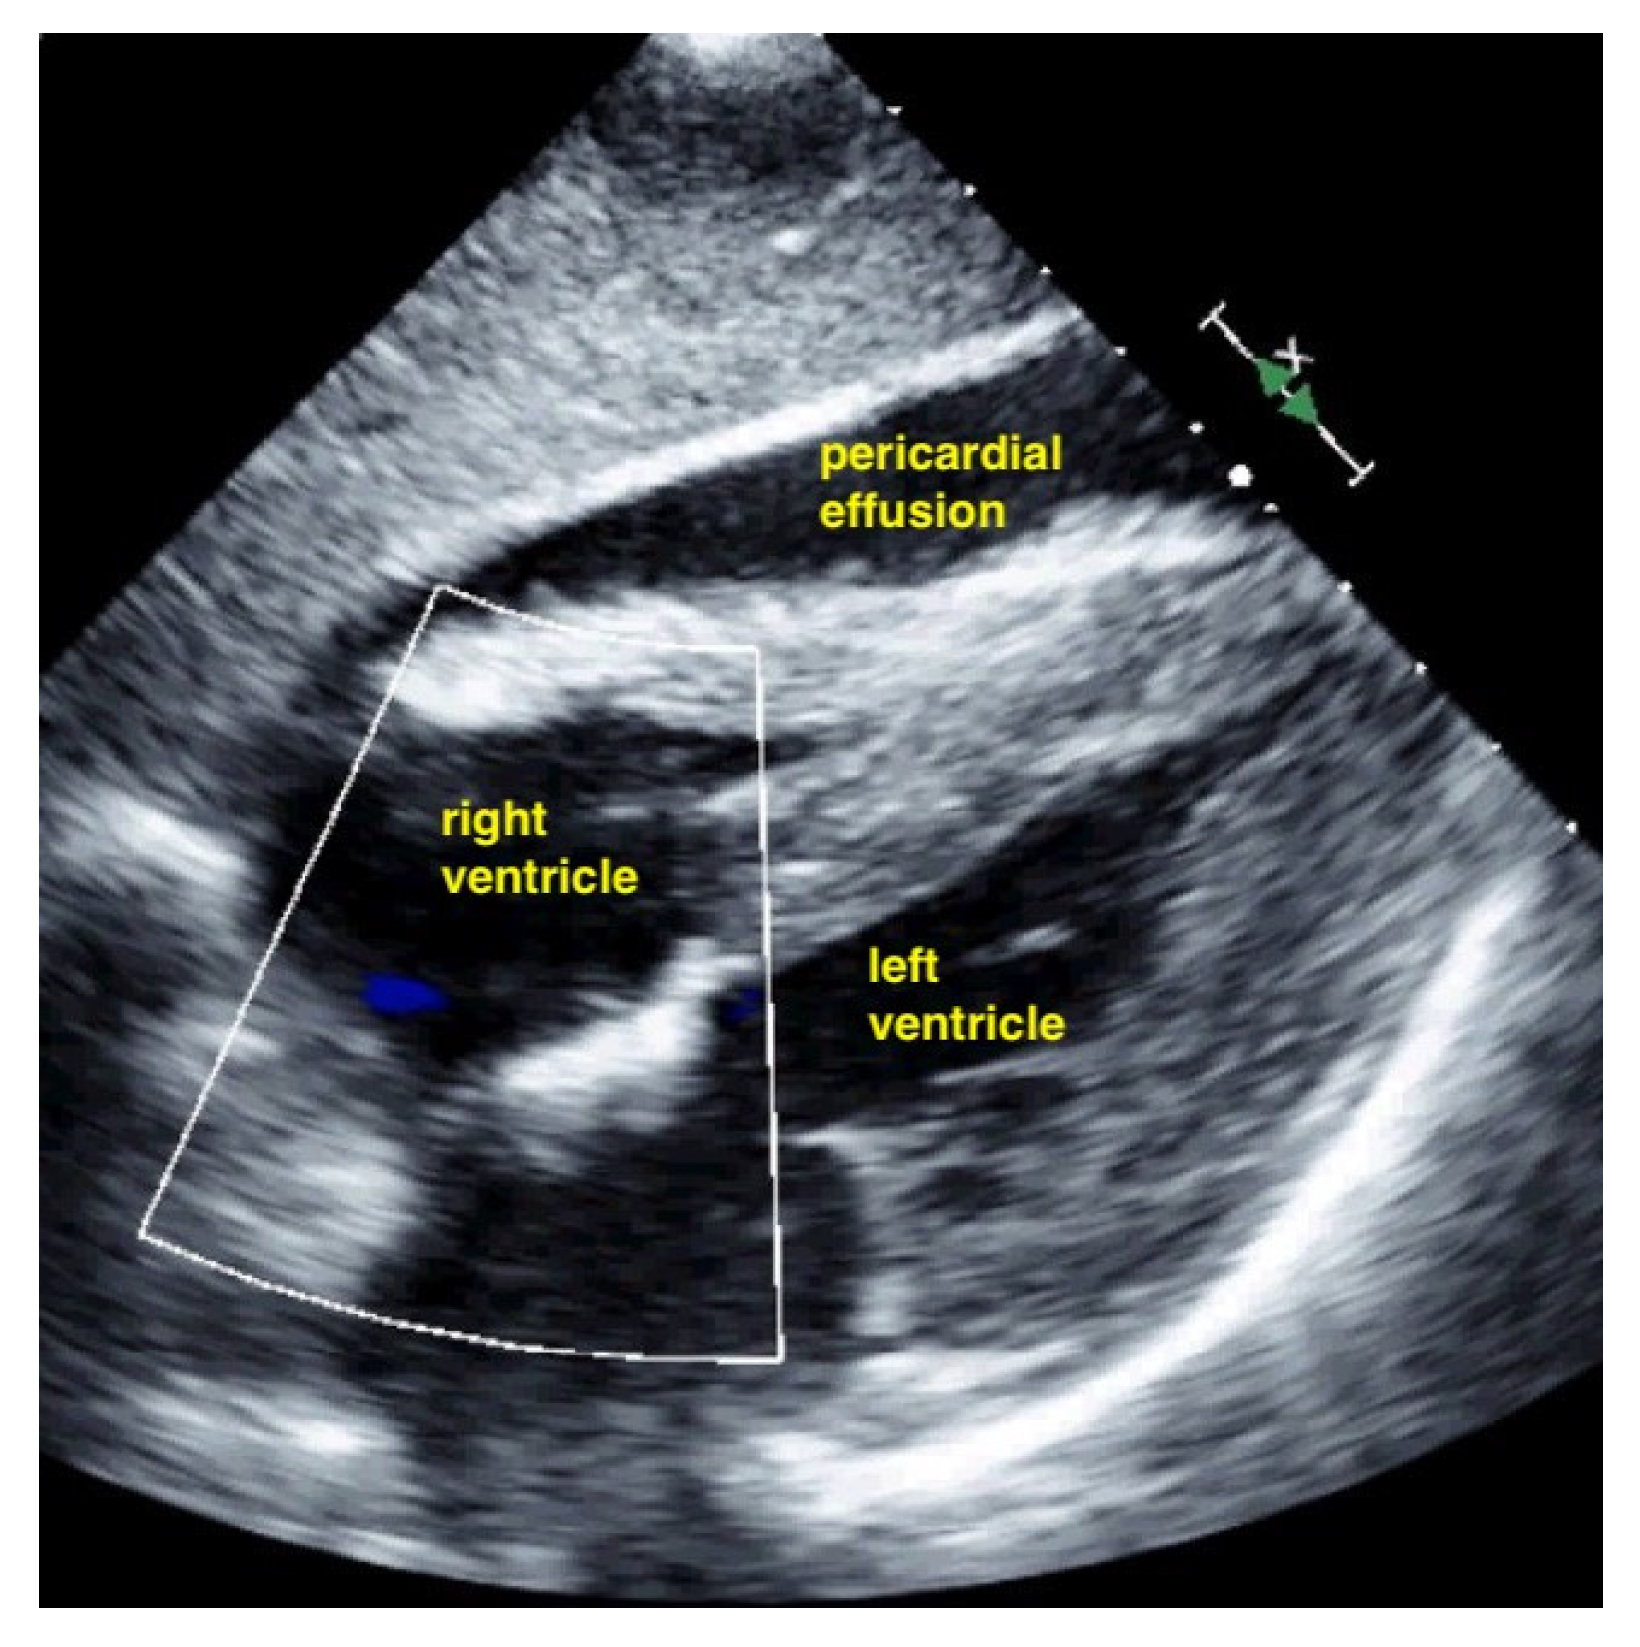

7.2.1. Pericardial Effusion

Pericardial effusions are best identified with a convex or sector probe in the subxiphoid or parasternal view. While it is important to simply note whether an effusion is present, sonographic and clinical (hypotension and tachycardia) evidence of cardiac tamponade should be sought. These include diastolic collapse of the right atrium free wall, followed by free wall collapse of the right ventricle as tamponade worsens. Both the apical and subcostal four-chamber views are ideal for this assessment. However, the subcostal window allows for a rapid transition to the proximal IVC view, which is dilated (>2 cm) and does not vary with respiration in cases of cardiac tamponade. Although many cases of medium and large pericardial effusions are obvious on ultrasound, there are notable exceptions. These include some hemorrhagic effusions which show significant coagulation, thus appearing echogenic on ultrasound, leading to frequent confusion with an epicardial fat pad or even a portion of the myocardial wall. Conversely, some epicardial fat pads may be confused with pericardial effusions, especially by novices. Differentiating between the two is easy by using anatomical knowledge. An epicardial fat pad does not extend enough inferiorly to be seen on a longitudinal IVC inlet view, while a pericardial effusion will in virtually all cases (Figure 7, Figure 8, Figure 9 and Figure 10).

Figure 7.

Pericardial effusion in parasternal long-axis view.

Figure 8.

Pericardial effusion in subxiphoidal view.

Figure 9.

Pericardial effusion in apical four chamber view compresses the right atrium slightly (RA = right atrium, LA = left atrium, RV = right ventricle, LV = left ventricle).

Figure 10.

Pericardial effusion in subxiphoidal view compresses the right ventricle.